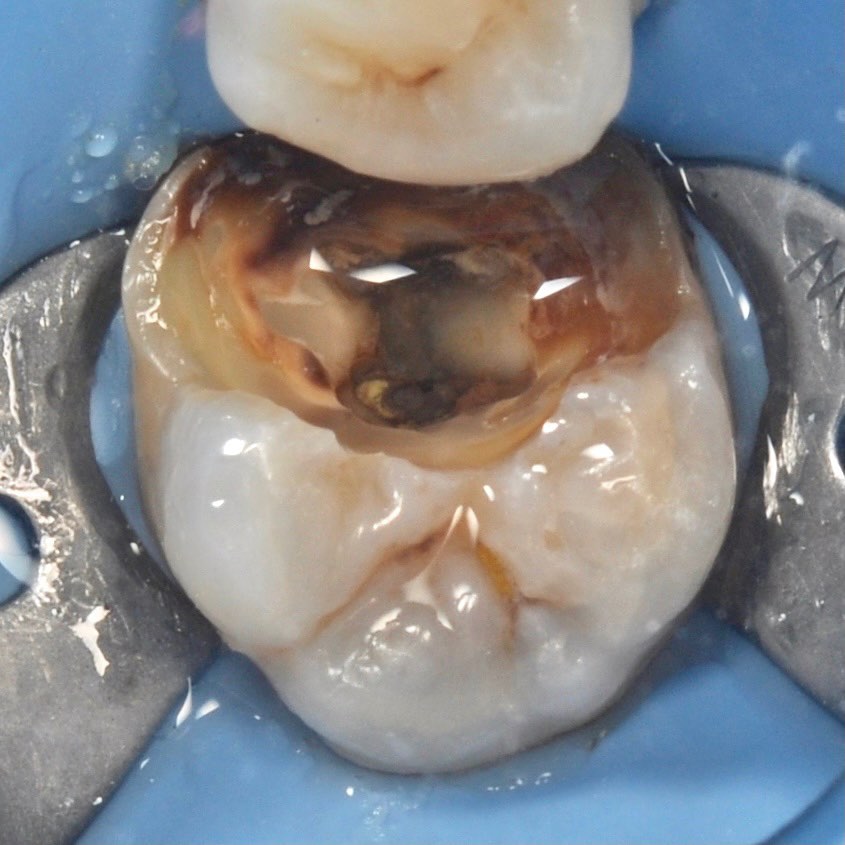

Unfortunately, inflammation inside tooth is a frequent problem. Initial inflammation is mainly caused with bacteria which destroy tooth reaching its center and penetrating into pulp. But there is also a secondary inflammation, which is not discussed with patients, but between the dentists only.

In fact, we are often applied by the patients who require repeated treatment of canals. It is important to realize that root canal has rather complicated structure, as it consist of both main canal and lots of branches like tree roots. Treatment of all the cavities and branches requires much time, special technique and chemical materials.

careful treatment of canals

Accurate determination of the geometry of the channels and their high-quality processing

caries removal

channel processing